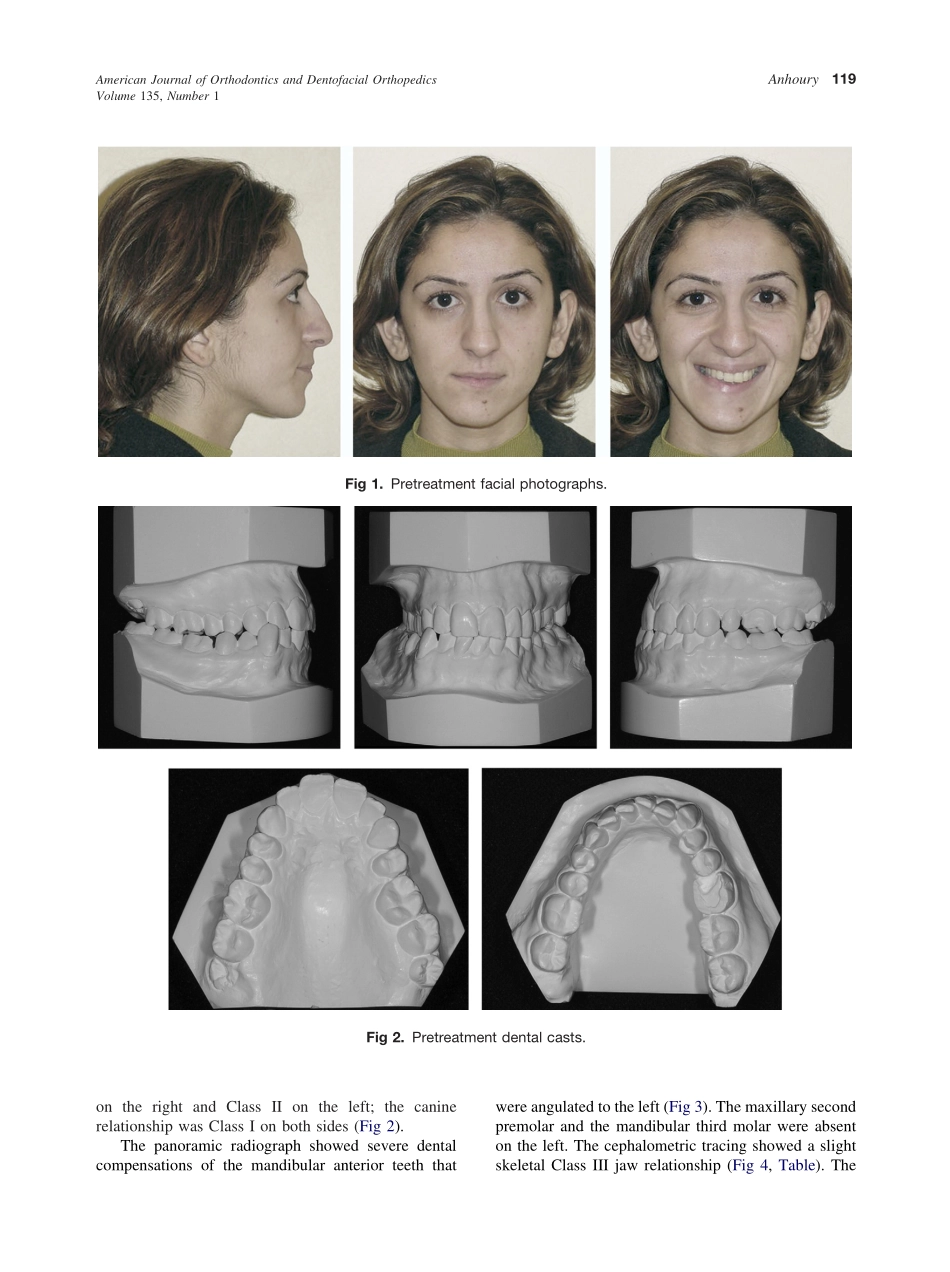

CASEREPORTNonsurgicaltreatmentofanadultwithmandibularasymmetryandunilateralposteriorcrossbitePatrickS.AnhouryBeirut,LebanonThepatientwasawoman,24years8monthsold,withmandibularasymmetryresultinginau...